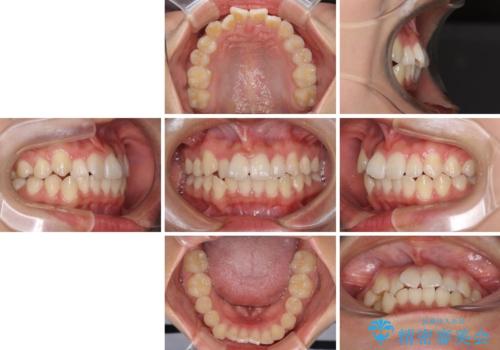

- 上下のデコボコと前歯のクロスバイトを改善したいとのことで来院された患者様です。

極力短期間で治療したいとのことで、ワイヤー装置による矯正治療を行うこととしました。

お住まいが遠方であったため、マウスピースによる矯正治療も提案しましたが、ご自身でのマウスピースの管理の面倒くささと、なるべく早く治療を終えたいとのことで、ワイヤー矯正を選択されました。